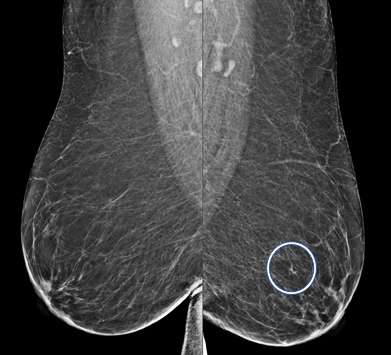

Asymmetry:

An asymmetry is a finding onlyseen on one projection3. Asymmetries that have been evaluated without suspicious features but persist are likely benign and can be managed with 6-month short-term imaging follow up.